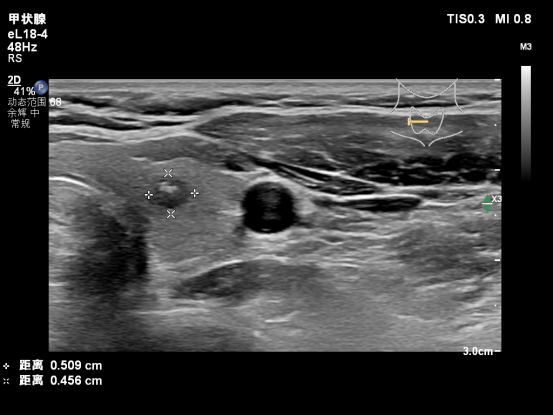

甲状腺结节射频消融 微创精准 不留疤痕 甲状腺结节手术担心留疤? 葫芦岛市第二人民医院 甲状腺疾病诊治中心 超声引导下经皮射频消融术 仅需“一针”即可精准消除结节 不留疤痕,更微创、更精准 守护您的健康与美观 精准诊断,量身定制治疗方案 48岁的张女士在体检中发现甲状腺结节,起初她十分焦虑:既担心结节恶化,又害怕传统手术会留下疤痕、影响甲状腺功能。经过多方咨询,最终慕名来到葫芦岛市第二人民医院甲状腺疾病诊治中心。 甲状腺超声专家门诊超声科王云霞主任、邓兆姝副主任为其完善检查,发现甲状腺存在两枚结节,分别为右叶0.9x0.5cm低回声结节,C-TI-RADS 4b类;左叶0.6x0.4cm囊性结节,C-TI-RADS 2类。 为进一步明确性质,团队为张女士实施了超声引导下细针穿刺活检。经病理检查和BRAF基因检测,确诊为恶性病变。综合她的病情与个人意愿,诊治中心没有直接选择传统手术,而是推荐了更适合她的射频消融治疗方案。这不仅能够彻底灭活病灶,还能最大限度保留甲状腺功能,真正实现“治疗与功能兼顾”。 一针消融,精准守护颈部结构 手术中,王云霞、邓兆姝主任团队先在甲状腺周围注入隔离液,为神经、血管等关键组织筑起一道“安全防护墙”。随后,在超声实时引导下,将消融针精准穿刺至结节部位进行治疗。整个过程患者始终发音清晰,无声音嘶哑等不适,真正做到了“精准消融、周围无忧”。 术后仅十分钟,团队立即为张女士进行超声造影复查。结果显示,消融区域在动脉期及静脉期均无造影剂灌注,呈现“无增强”表现,证实病灶已完全灭活,治疗效果立竿见影。张女士术后恢复顺利,当天即可回家,真正体验到了“当天治疗、当天回家”的便捷。 患者术后 用针眼大小的入口完成治疗,不留疤痕,不影响颈部外观,同时能有效保留正常甲状腺功能,大大缩短了康复时间,提升了治疗体验。 多元选择,一体化诊疗实现个体化治疗 葫芦岛市第二人民医院超声科在王云霞主任带领下,不断精进技术、突破瓶颈。邓兆姝副主任赴北京中日友好医院超声科进修深造后,突破超声诊断技术瓶颈,将前沿诊疗理念与技术引入临床,显著提升了甲状腺穿刺活检的成功率与确诊率。针对甲状腺彩超结节分类4a类以上患者,能够快速精准区分良恶性肿瘤,推动科室甲状腺恶性肿瘤诊断水平实现质的飞跃。 与此同时,超声科积极拓展服务边界,开展甲状腺超声造影、甲状腺囊肿固化治疗、甲状腺消融治疗等多项新技术。自2025年4月甲状腺疾病诊治中心成立以来,甲状腺超声门诊已累计完成穿刺活检近百例,病理及基因检测符合率高达98%,让辽西地区患者在家门口就能享受高水平甲状腺疾病诊治服务。 人民医院 人民名医 王云霞 副主任医师 ·葫芦岛市第二人民医院超声科主任 ·中国研究型医院学会委员 ·中国研究型医院学会肌骨及浅表专业委员会超声学组委员 ·中国女医师协会委员 ·辽宁省超声医学工程学会理事会理事 ·辽宁省医师协会超声分会委员会委员 ·辽宁省免疫学会超声治疗分会委员 ·辽宁省中西医结合委员会超声分会委员 ·葫芦岛市医学会超声委员会副主委 专业特色:擅长心血管和外周血管、浅表器官和腹部及产前超声诊断;超声引导下前列腺癌、肺癌及淋巴癌穿刺活检病理标本的采集;心包、胸(腹)腔积液的穿刺引流;介入治疗肝肾脓肿胆囊置管引流;超声引导下甲状腺、乳腺结节的细胞学及组织学穿刺活检;甲状腺、卵巢及肝肾囊肿的固化治疗等,盆底超声、实质器官及血管超声造影以及部分肌骨超声检查。发表核心级论文2篇、国家级论文6篇,参与编撰图书一部,《医学影像诊断指南》副主编。 邓兆姝 副主任医师 ·葫芦岛市第二人民医院超声科副主任 ·中国研究型医院学会肌骨及浅表超声科专业委员会青年委员 ·辽宁省医学会超声医学分会委员 专业特色:甲状腺、乳腺疾病超声精准诊断;超声引导下穿刺活检(细针/粗针);全身脏器超声造影;甲状腺、乳腺及其它脏器囊肿硬化治疗;甲状腺癌术后超声随访评估;独立开展甲状腺结节微波/射频消融治疗。 技术特色:开展甲状腺结节多模态超声评估(弹性成像+造影)、消融治疗全程超声监控等特色技术,以“精准诊断+微创治疗”为临床特色。